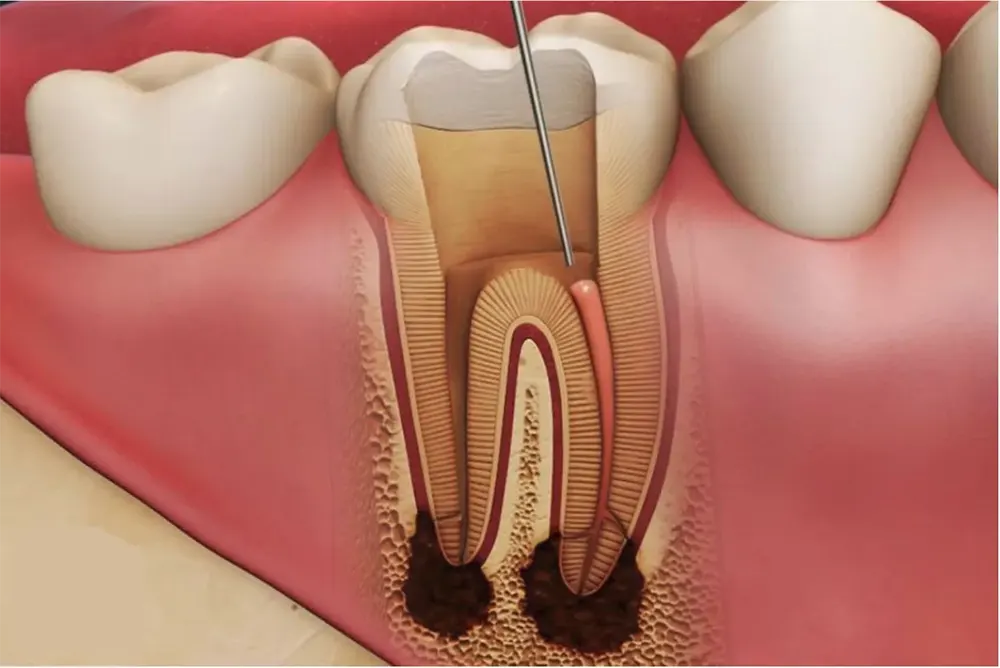

Bệnh nhân sẽ được Tiến sĩ – Bác sĩ thăm khám trực tiếp và đánh giá tình trạng tổn thương, bác sĩ có thể kiểm tra đáp ứng tủy bằng dụng cụ chuyên sâu và chụp X-Quang răng. Đây là bước làm cần thiết để biết được tình trạng viêm tủy, mức độ nhiễm trùng và dữ liệu cách thức điều trị tủy răng. Bác sĩ sẽ lên kế hoạch về thời gian, chi phí, điều trị nội khoa phối hợp và các phương án phục hồi sau khi chữa tuỷ để đảm bảo chức năng bình thường của răng.

Điều trị tuỷ có thể đau hoặc không đau tuỳ vào cơ địa của từng khách hàng. Trong bất kỳ trường hợp nào khách hàng cảm thấy khó chịu, chúng tôi sẽ thực hiện gây tê vô cảm để khách hàng cảm thấy thoải mái và an tâm nhất. Ở giai đoạn này, bác sĩ sẽ tỉ mỉ làm sạch, tạo dạng và trám bít toàn bộ ống tủy bằng vật liệu tương hợp sinh học. Giai đoạn này có thể kéo dài trong 1 hoặc vài buổi hẹn.